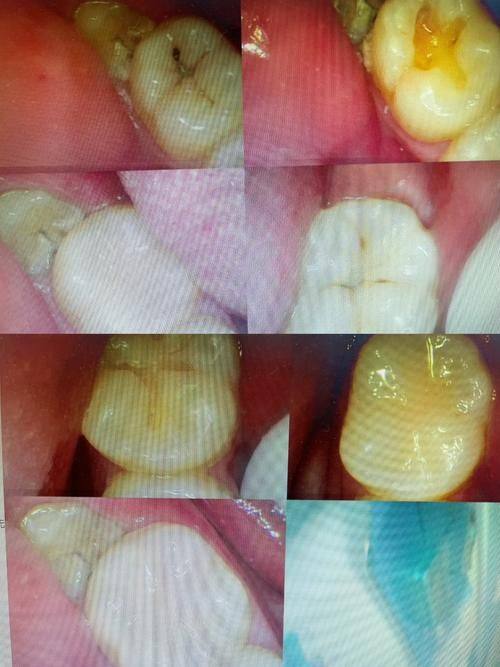

3. 个性化诊疗:医生会根据每位患者的口腔状况和需求,制定个性化的治疗方案,确保治疗成效达到至佳。

2. 我的牙齿有缺失,一直想做种植牙。来到简爱芽口腔后,医生根据我的情况推荐了合适的种植方案。手术过程特别顺利,术后修复也特别快。现在种植牙用着和真牙一样,咀嚼功能完全不受影响,感觉这里的技术真的特别棒!

4. 我有牙齿敏感的问题,在简爱芽口腔做了牙齿修复。医生特别专精,详细分析了我的问题,并给出了有效的治疗方案。修复后牙齿敏感的情况得到了明显改善,而且牙齿看起来也特别自然,对这次治疗非常满意。